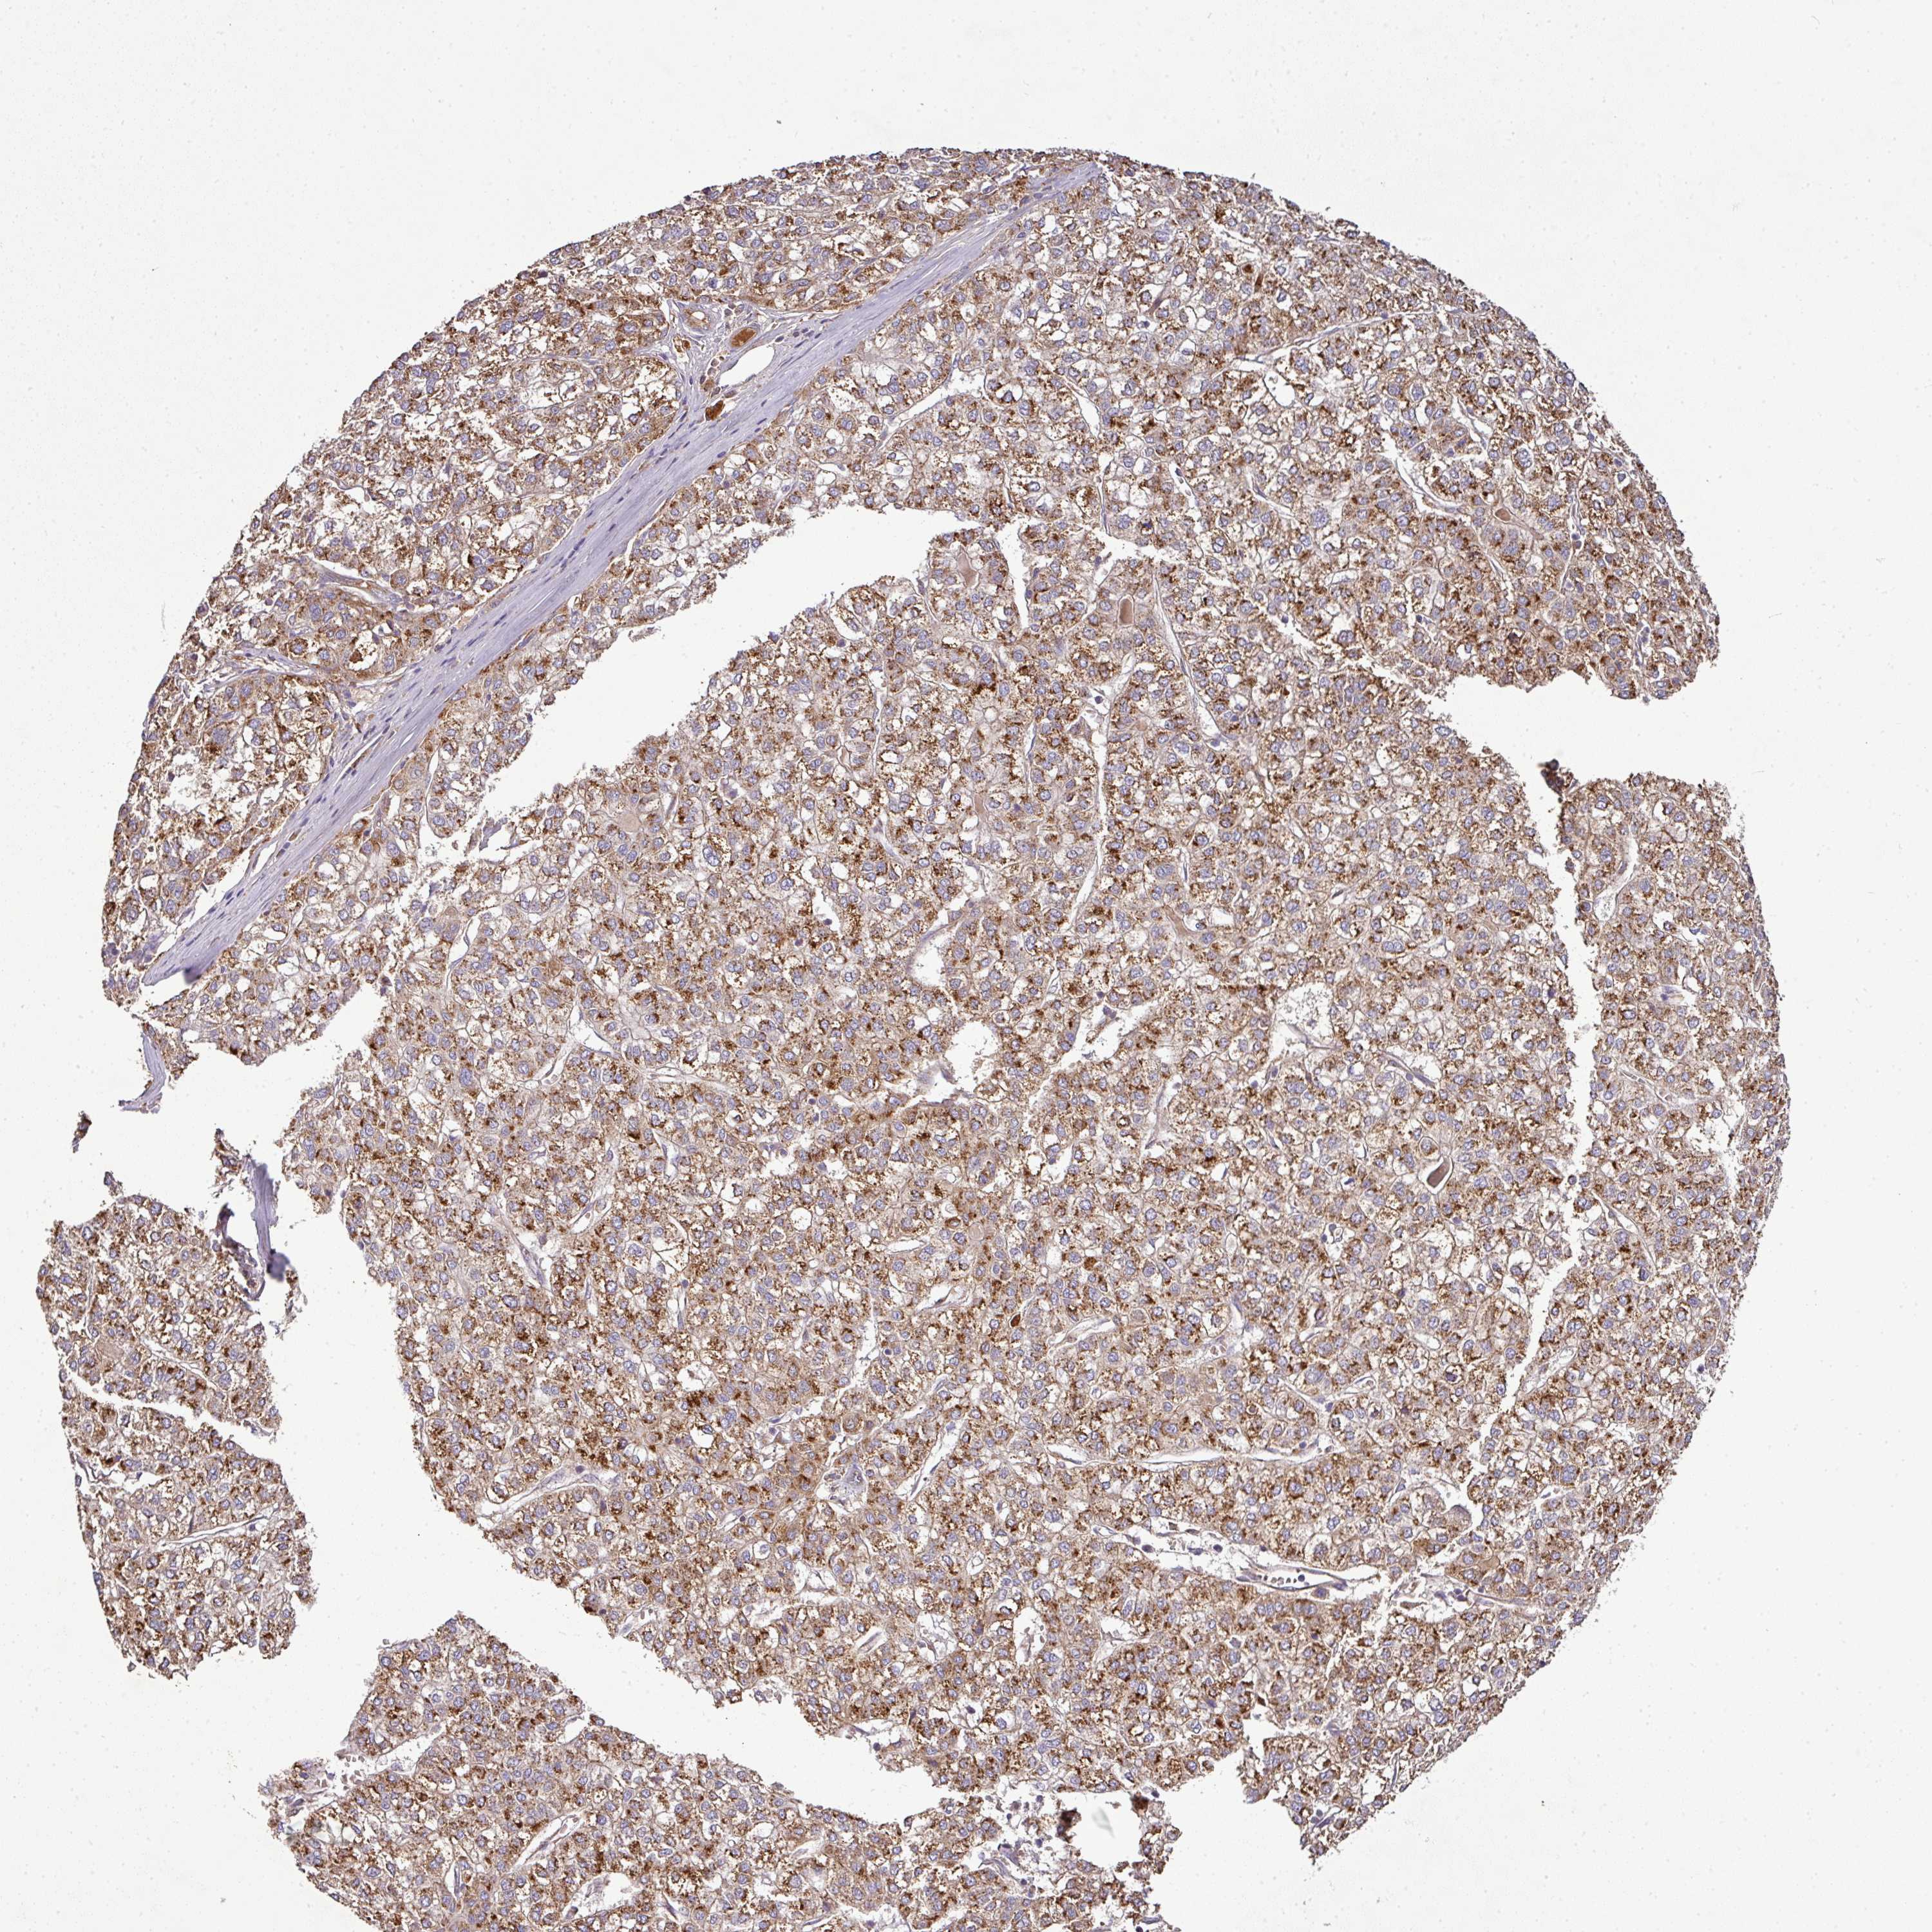

LIVER CANCER - Protein expressioni

A mouse-over function shows sample information and annotation data. Click on an image to view it in a full screen mode. Samples can be filtered based on level of antibody staining by selecting one or several of the following categories: high, medium, low and not detected. The assay and annotation is described here.

Note that samples used for immunohistochemistry by the Human Protein Atlas do not correspond to samples in the TCGA dataset.

Antibody stainingi

Antibody staining in the annotated cell types in the current human tissue is reported as not detected, low, medium, or high, based on conventional immunohistochemistry profiling in selected tissues. This score is based on the combination of the staining intensity and fraction of stained cells.

Each image is clickable and will lead to virtual microscopy that enables deeper exploration of all samples and also displays staining intensity scores, fraction scores and subcellular localization as well as patient and tissue information for each sample.

Antibody HPA045954

Antibody HPA076632

Antibody CAB003686

Staining

High

Medium

Low

Not detected

Intensity

Strong

Moderate

Weak

Negative

Quantity

>75%

75%-25%

<25%

None

Location

Nuclear

Cytoplasmic/membranous

Cytoplasmic/membranous,nuclear

Carcinoma, Hepatocellular, NOS

Cholangiocarcinoma

Adenocarcinoma, NOS